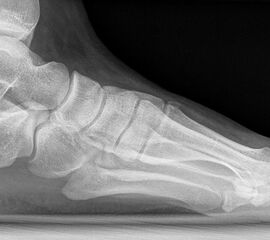

Röntgen

Standard ist die belastete Röntgenaufnahme des Fußes dorso-plantar und seitlich. Günstig ist eine Röhrenkippung von 10°-20°, um die Gelenke der Lisfranc-Linie einsehen zu können.

Ergänzend kann eine Schrägaufnahme hilfreich sein. Bei Metatarsalgien oder Pathologien der Sesambeine liefert die Sprinteraufnahme zusätzliche Informationen. Bei einer Pes planovalgus Fehlstellung wird ergänzend ein Saltzman view durchgeführt.

• Elevation/ Plantarisierung I. Strahl

• Pes metatarsus adductus